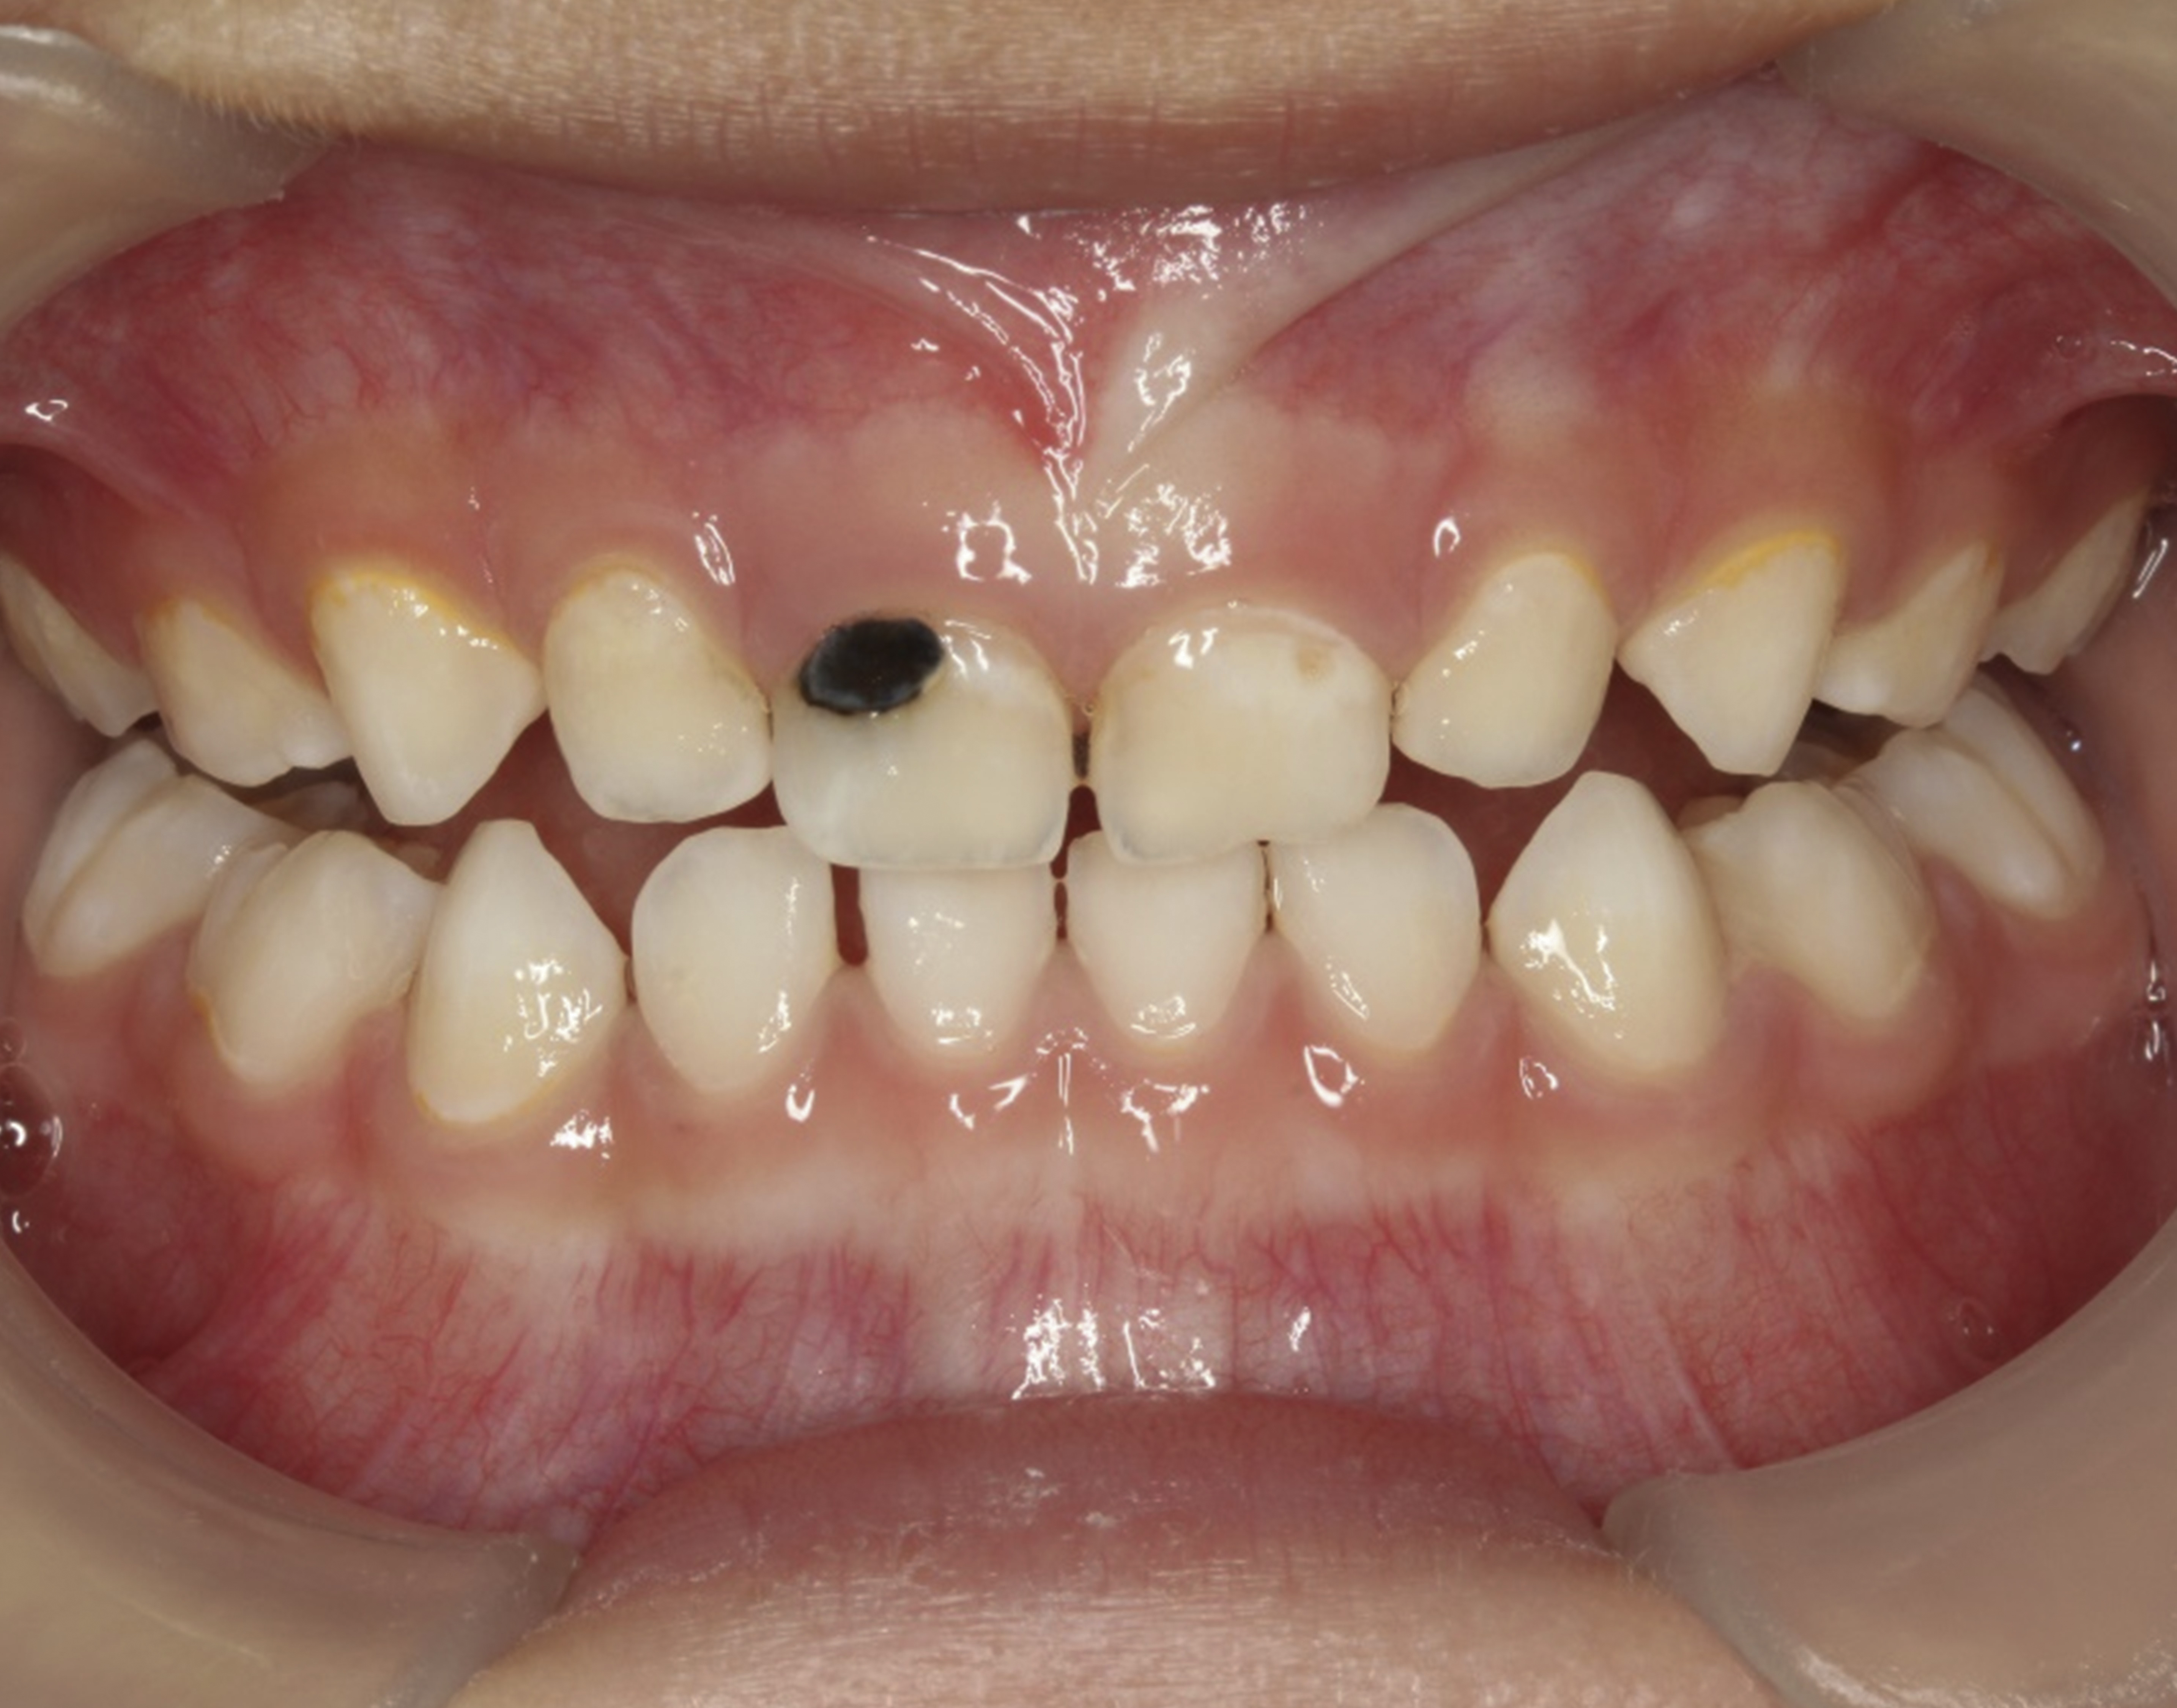

The inherent disadvantage of SDF is that the caries lesions will be stained black after SDF application. SDF stops caries progression by forming a hard, blackened, impermeable layer on the tooth surface that is resistant to caries (Figure 5 through Figure 9). The authors’ clinical observations are that the darker the color, the more likely the caries arrested. Some patients may not be pleased with the esthetics of this treatment outcome; therefore, it is important to inform the patients and parents (for child patients) about this treatment outcome. Moreover, SDF can stain clothes and the skin of the body. Though it does not cause any pain or damage, an SDF stain on skin cannot be easily washed away. It takes around 7 days for it to disappear, and the stain on clothes is permanent.22

There is no consensus on the frequency of application, and 38% SDF has been used annually or biannually on clinical trials in children23,31,33,34 and in elderly.30,35 Yee and his co-worker found one-off application of 12% SDF was ineffective in arresting caries in children.31 The present authors applied 38% SDF weekly for 3 weeks to speed up the process of caries arrest and for treatment of rampant caries.36 One of the present authors’ case reports demonstrated that three weekly applications of 38% SDF can arrest rampant caries and relieve pain from hypersensitivity on a teenager. The SDF-treated caries were found arrested, and they turned coal black in appearance (Figure 9).

Fig 8. Use of 38% SDF to arrest rampant caries in a young teenager. Fig 8: Pre-treatment intraoral frontal view of rampant caries. Fig 9: Frontal view of arrested caries after consecutive application of SDF for 3 weeks. (images from Chu, et al, 201436 [reprinted with approval])

Fig 9. Use of 38% SDF to arrest rampant caries in a young teenager. Fig 8: Pre-treatment intraoral frontal view of rampant caries. Fig 9: Frontal view of arrested caries after consecutive application of SDF for 3 weeks. (images from Chu, et al, 201436 [reprinted with approval])